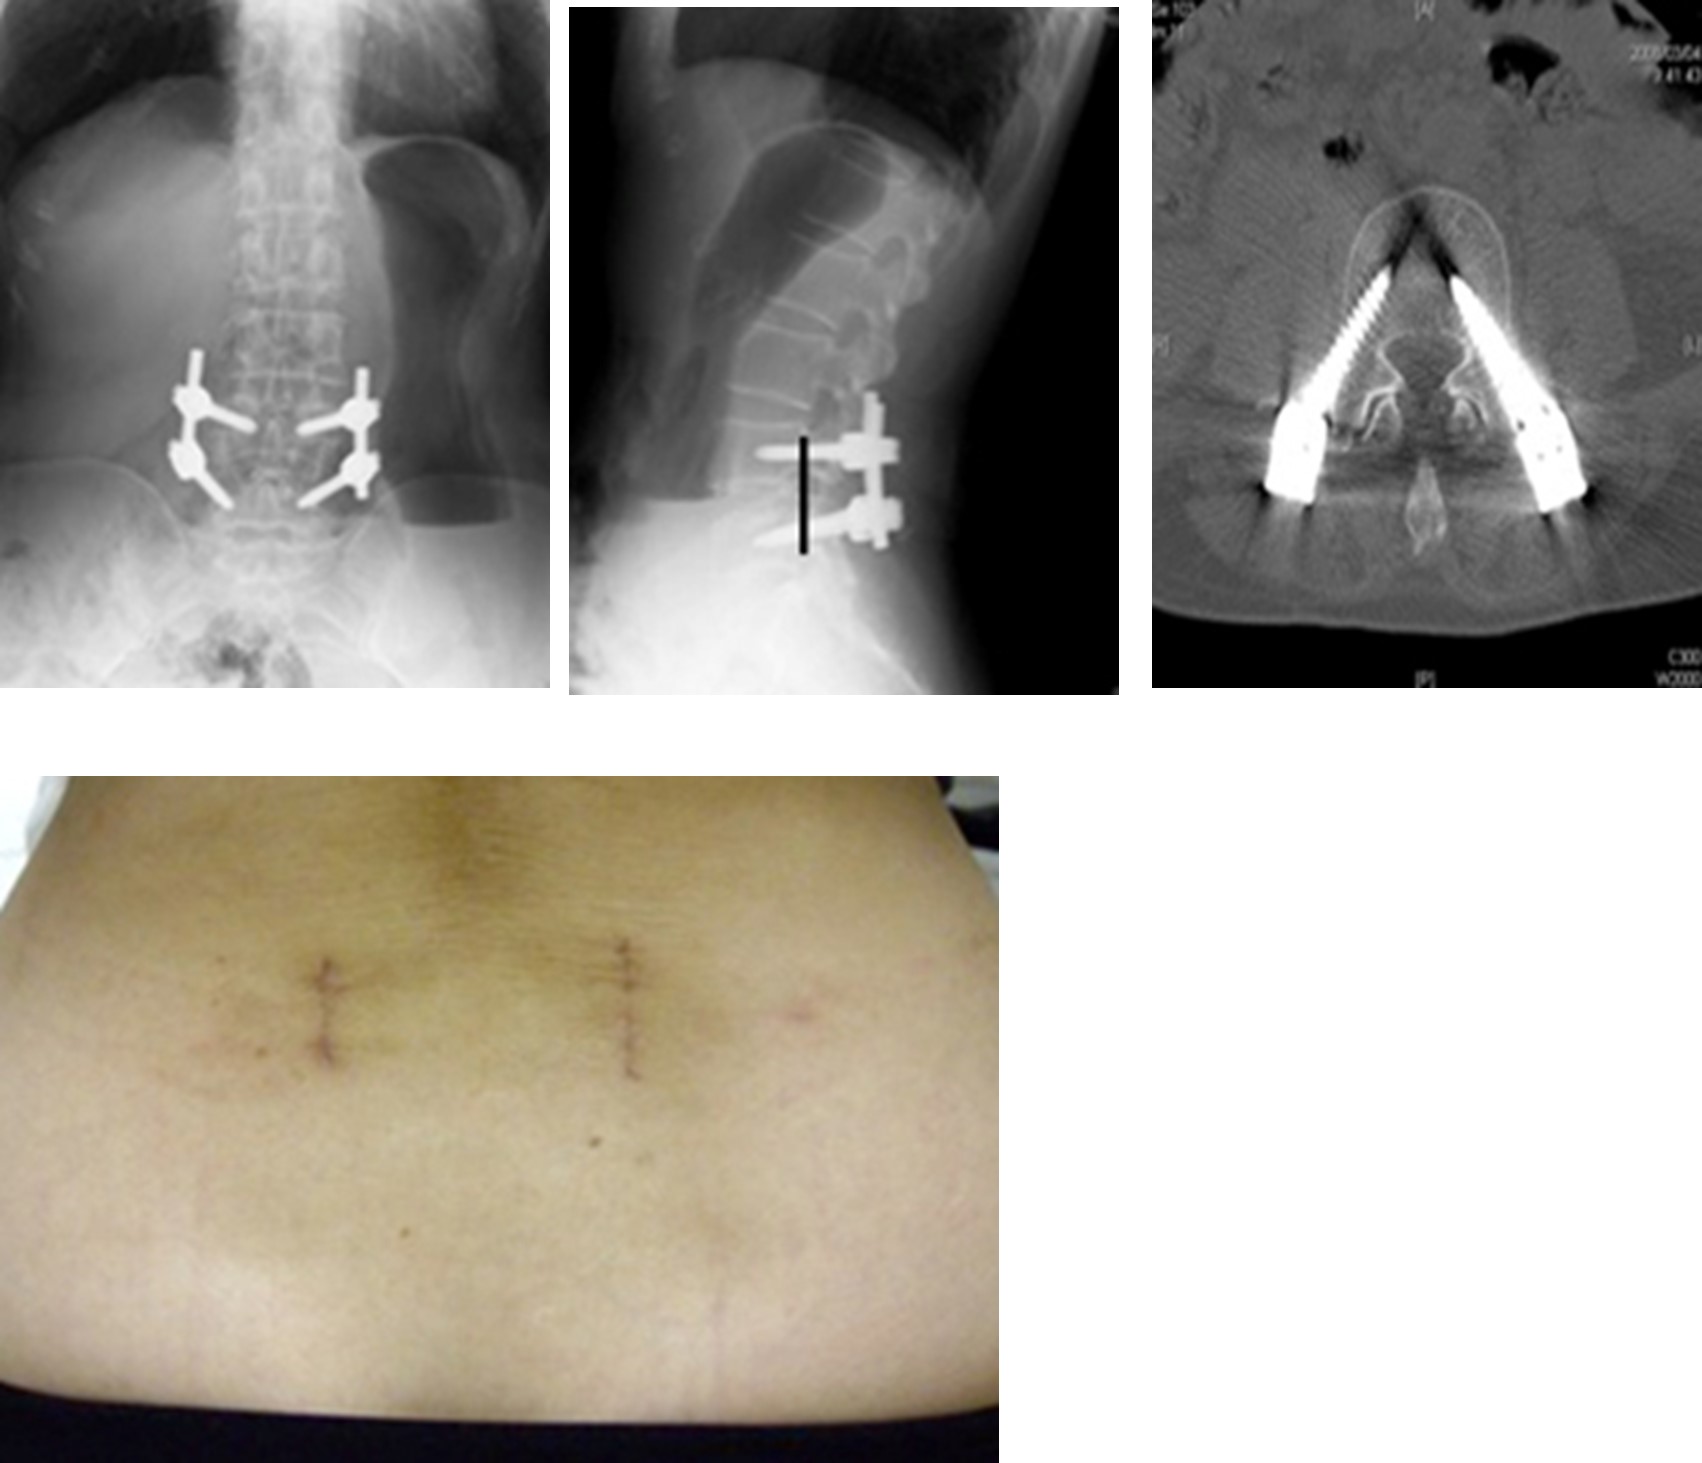

図 (上段左、まん中、右)手術後:ずれているせぼねが矯正されています。(線で示す部分)

(下段)傷は両サイドに縦に約3cm弱と小切開です。皮膚切開が小さいだけでなく、皮下の筋肉などの軟部組織の損傷が極めて小さいことが特徴です。